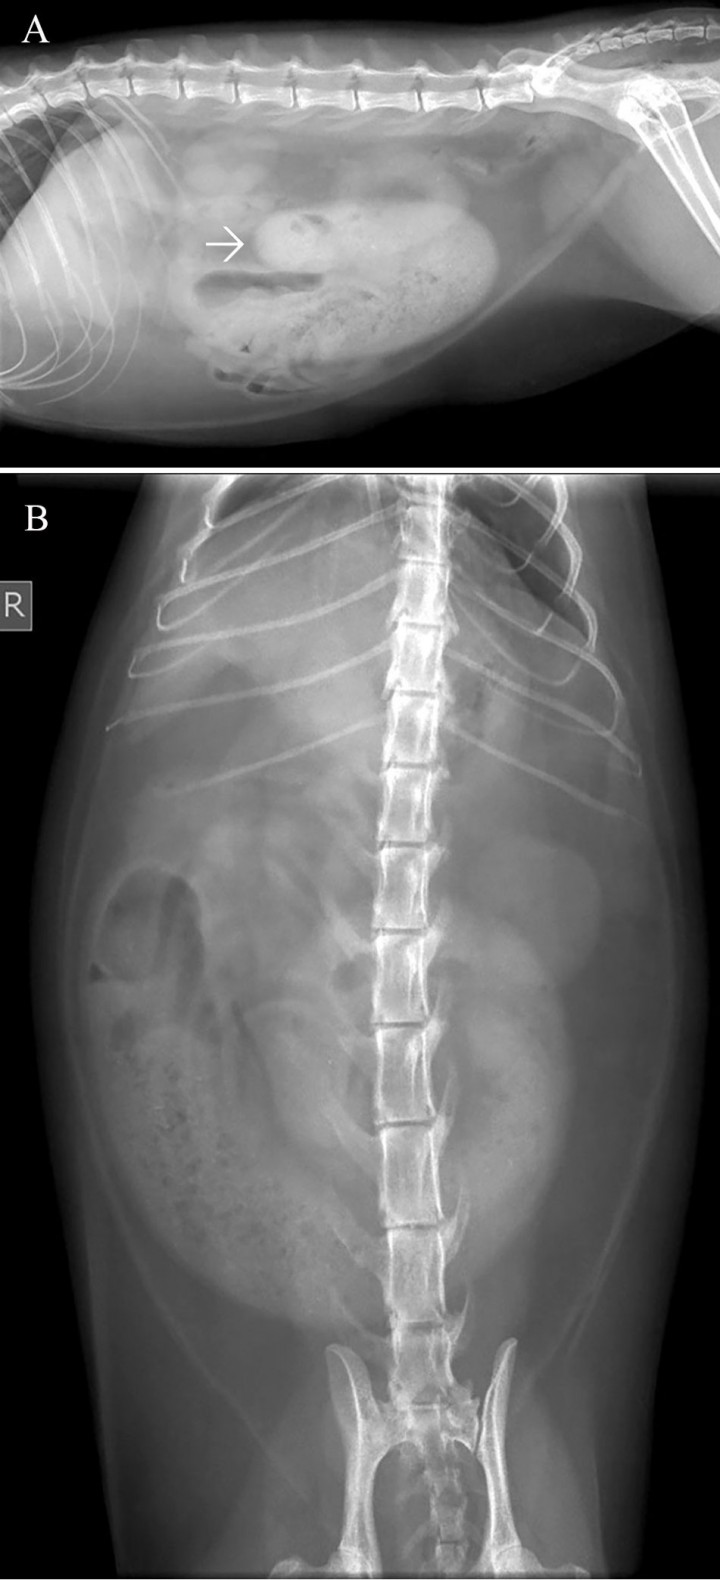

En el abdomen medio, desde el lado derecho al izquierdo, se observa un asa de intestino delgado distendida (ratio diámetro del asa respecto a la altura L4 = 6, valor de referencia 1), con un contenido de opacidad mixta y aspecto granular con pequeñas estructuras radiopacas, compatible con un signo de grava (Fig. 2).

<p>Mismas radiografías que en la Figura 1. Se observa el asa distendida (flechas) con un contenido de opacidad mixta y aspecto granular con pequeñas estructuras radiopacas, compatible con un signo de grava.</p>

Mismas radiografías que en la Figura 1. Se observa el asa distendida (flechas) con un contenido de opacidad mixta y aspecto granular con pequeñas estructuras radiopacas, compatible con un signo de grava.

El signo de grava es compatible con íleo mecánico debido a una obstrucción parcial y crónica. Los diagnósticos más probables son neoplasia intestinal (linfoma, adenocarcinoma, mastocitoma), fibroplasia esclerosante eosinofílica gastrointestinal felina (FGESF), enteritis piogranulomatosa y adherencias, y, como diagnóstico menos probable, enfermedad inflamatoria intestinal (EII).